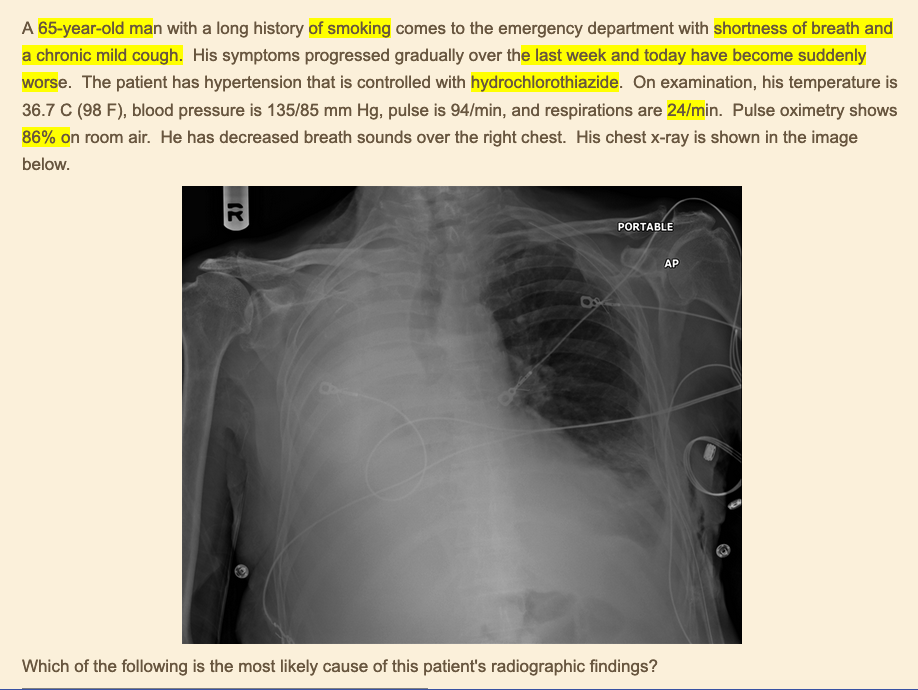

diagnosis?

clinical presentation